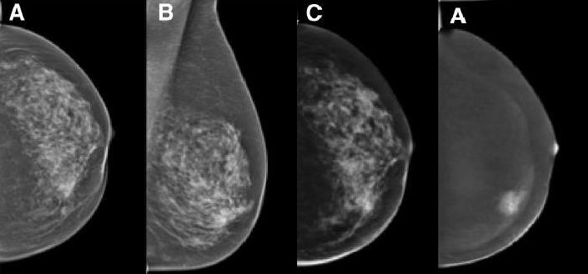

Dual-energy (DE) contrast-enhanced mammography is one of the latest developments in breast care. Imaging with contrast agents in breast cancer has been described in MRI and CT. However, high costs, limited availability and high radiation doses have led to the development of contrast-enhanced spectral mammography (CESM).

The research team focusing on the diagnosis of breast cancer has a vast wealth of experience with all the imaging modalities currently used for evaluation of the breast, including fine-needle aspiration and/or percutaneous biopsies using stereotaxis or ultrasound guidance. Our unit serves as the largest screening and assessment centre of the national breast-screening programme in Tyrol. Approximately 10,000 mammograms and breast ultrasound studies are performed each year.